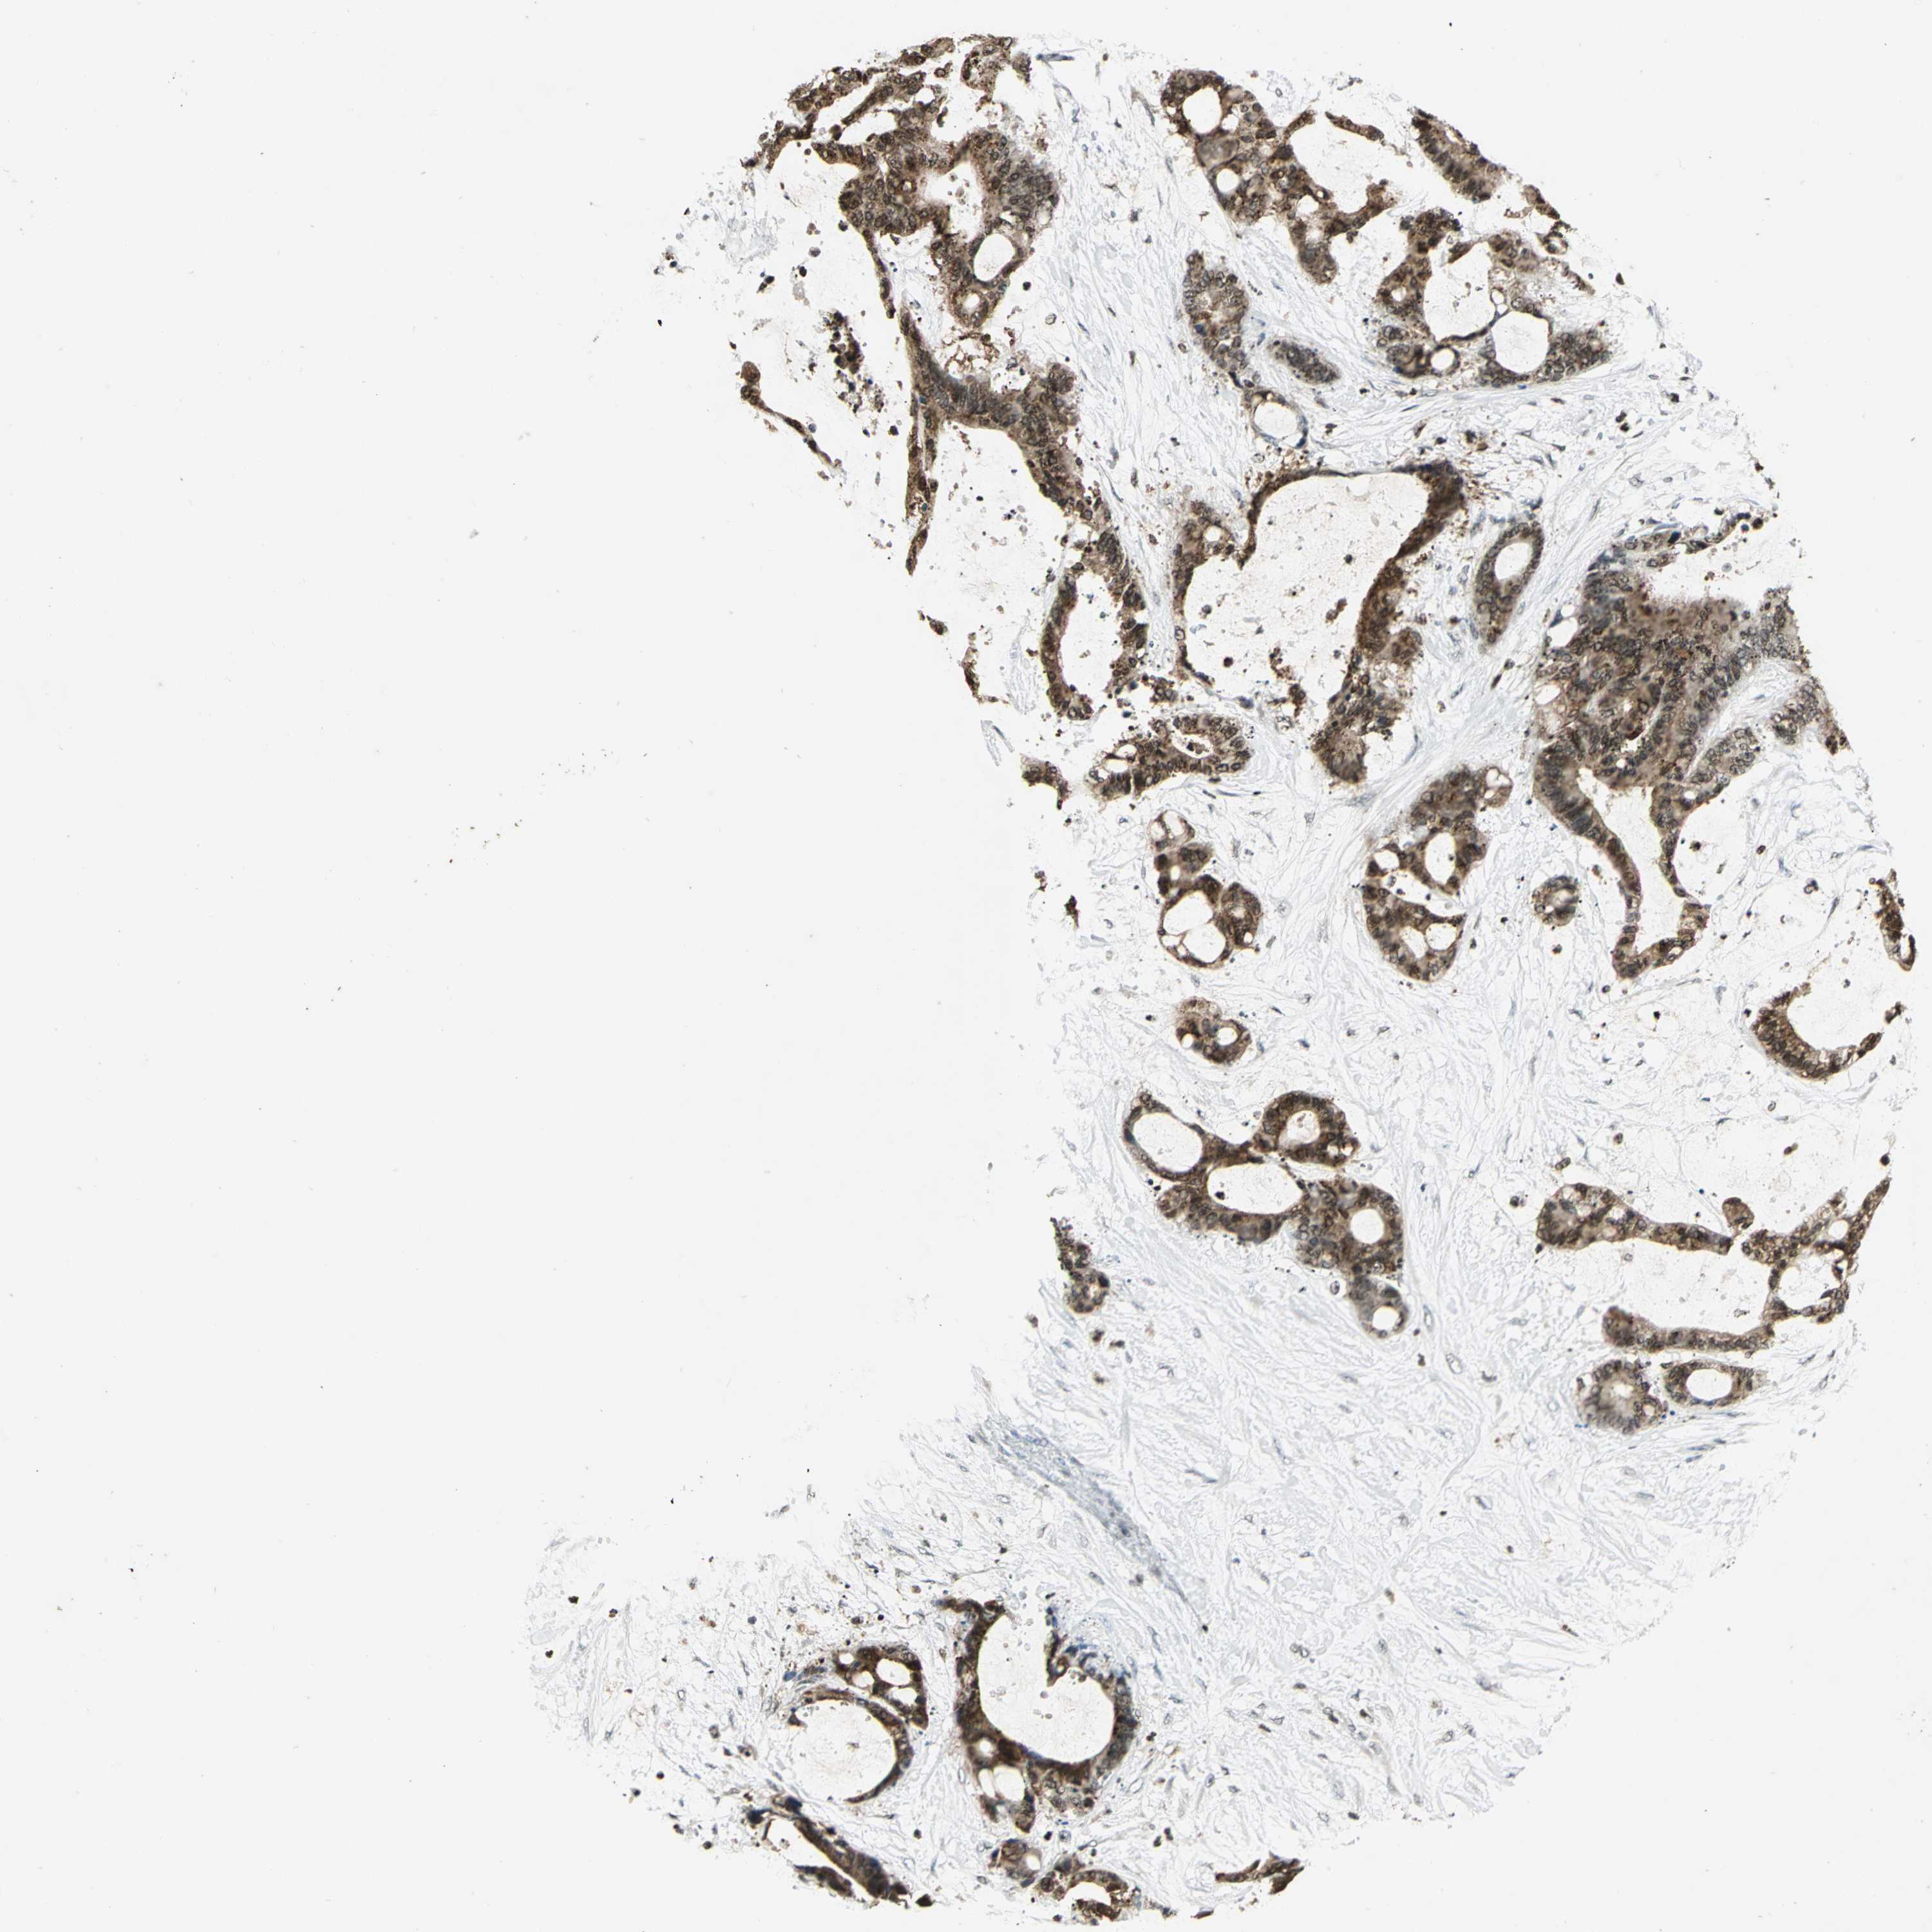

LIVER CANCER - Protein expressioni

A mouse-over function shows sample information and annotation data. Click on an image to view it in a full screen mode. Samples can be filtered based on level of antibody staining by selecting one or several of the following categories: high, medium, low and not detected. The assay and annotation is described here.

Antibody stainingi

Antibody staining in the annotated cell types in the current human tissue is reported as not detected, low, medium, or high, based on conventional immunohistochemistry profiling in selected tissues. This score is based on the combination of the staining intensity and fraction of stained cells.

Each image is clickable and will lead to virtual microscopy that enables deeper exploration of all samples and also displays staining intensity scores, fraction scores and subcellular localization as well as patient and tissue information for each sample.

Antibody HPA003162

Antibody CAB005191

Staining

High

Medium

Low

Not detected

Intensity

Strong

Moderate

Weak

Negative

Quantity

>75%

75%-25%

<25%

None

Location

Nuclear

Cytoplasmic/membranous

Cytoplasmic/membranous,nuclear

Carcinoma, Hepatocellular, NOS

Cholangiocarcinoma